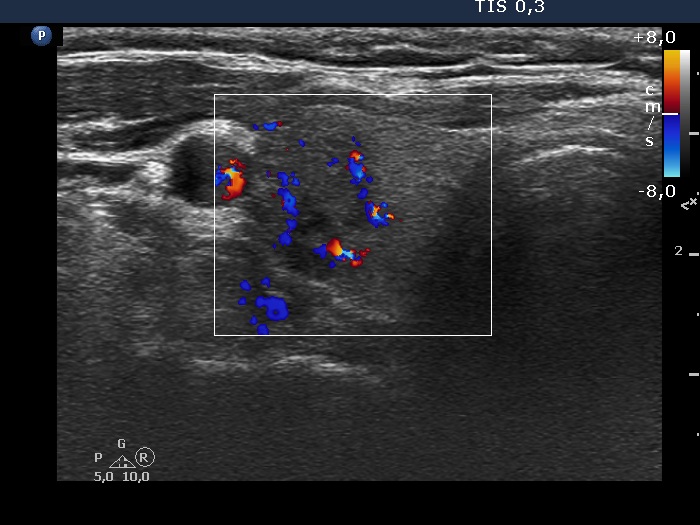

Ultrasonography. The thyroid was echonormal. There were several hypoechogenic nodules in the right lobe. One of the nodules had spiculations. There was a hypoechogenic nodule in the lower part of the right lobe. This lesion presented micro- and macrocalcifications.

Cytology was performed both from the hypoechoic large lesion and from the nodule in the lower pole. The diagnosis was in both cases benign, colloid goiter.

Comment. The hypoechoic mass in the right lobe presented undulated margins of non-pathological cause. One of the nodules of this mass had irregular, spiculated borders.